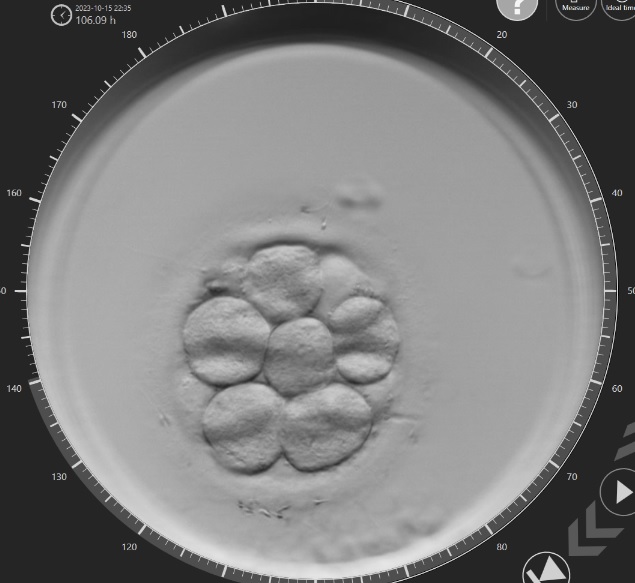

Durante el día 3 de desarrollo ocurre usualmente la activación del genoma embrionario y en el día 5, cuando el embrión llega a estado de blastocisto, se produce la implantación. No todos los embriones formados en un tratamiento de FIV llegan a blastocisto, solamente lo alcanzan los que tienen más posibilidades de implantación. Es por esto que actualmente la recomendación es transferir un embrión único en estadio de blastocisto.

Por lo tanto, al no existir evidencia que demuestren que la calidad de los embriones en día 3 tenga influencia en la clasificación en estadio de blastocisto y su potencial de implantación, se decidió no valorar más la calidad embrionaria en el día 3 y valorarla solamente en el día 5.